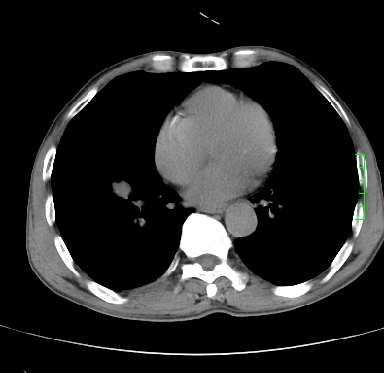

m,73y。膝关节疼痛伴双下肢水肿。入院常规胸片发现结节灶。增强为静脉期。

浅分叶、棘突,考虑右下肺周围型肺癌

考虑周围型肺癌  ,双上肺结核。

肿块周围可见局限性气肿,考虑肺癌可能性大。双肺上叶继发型肺结核。

指套征,强化明显,近侧肺组织局限性肺气肿,考虑支气管类癌,慢支、肺气肿、双上陈旧性tb、冠脉钙化。

1)考虑右肺下叶周围型肺癌。2)右肺上叶及左肺感染性病变(结核可能)。3)肺气肿。4)冠状动脉钙化。